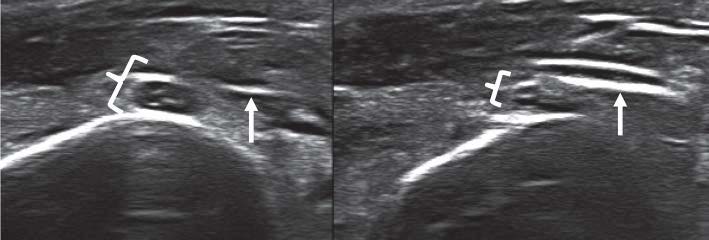

При полном повреждении нервного ствола на эхограмме визуализировались два конца нерва с отсутствием непрерывных контуров эпиневрия между ними и наличием гипоэхогенной зоны дефекта (рис. 1). В зависимости от сроков травмы на центральном конце нерва имелась посттравматическая неврома различных размеров, которая определялась в виде гипоэхогенного образования булавовидной формы. Чем более застарелая травма, тем ярче были выражены признаки дистрофических изменений как центрального, так и периферического концов нерва, которые проявлялись снижением эхогенности и нарушением дифференциации внутренней структуры.

Рис. 1. Продольная эхограмма. Полное повреждение локтевого нерва на уровне нижней трети предплечья с наличием гипоэхогенной зоны дефекта (стрелка) между концами нервного ствола